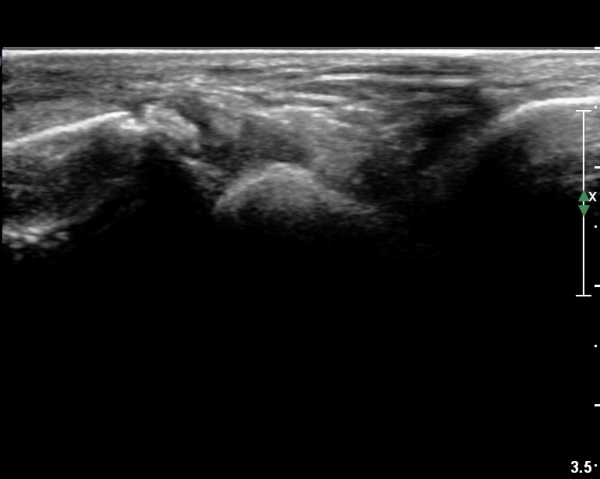

Àü°ÅºñÀδë Á¾´Ü¸é°Ë»ç¿¡¼­ ºñ°ñ ºÎÂøºÎ Àü°ÅºñÀδëÀÇ Àú¿¡ÄÚºÎÁ¾°ú ÀÎ´ë ¸»´ÜºÎ¿¡¼­

ºñ°ñÀÇ °ß¿­°ñÀýÀÌ °üÂûµÈ´Ù(»çÁø 3, 4).